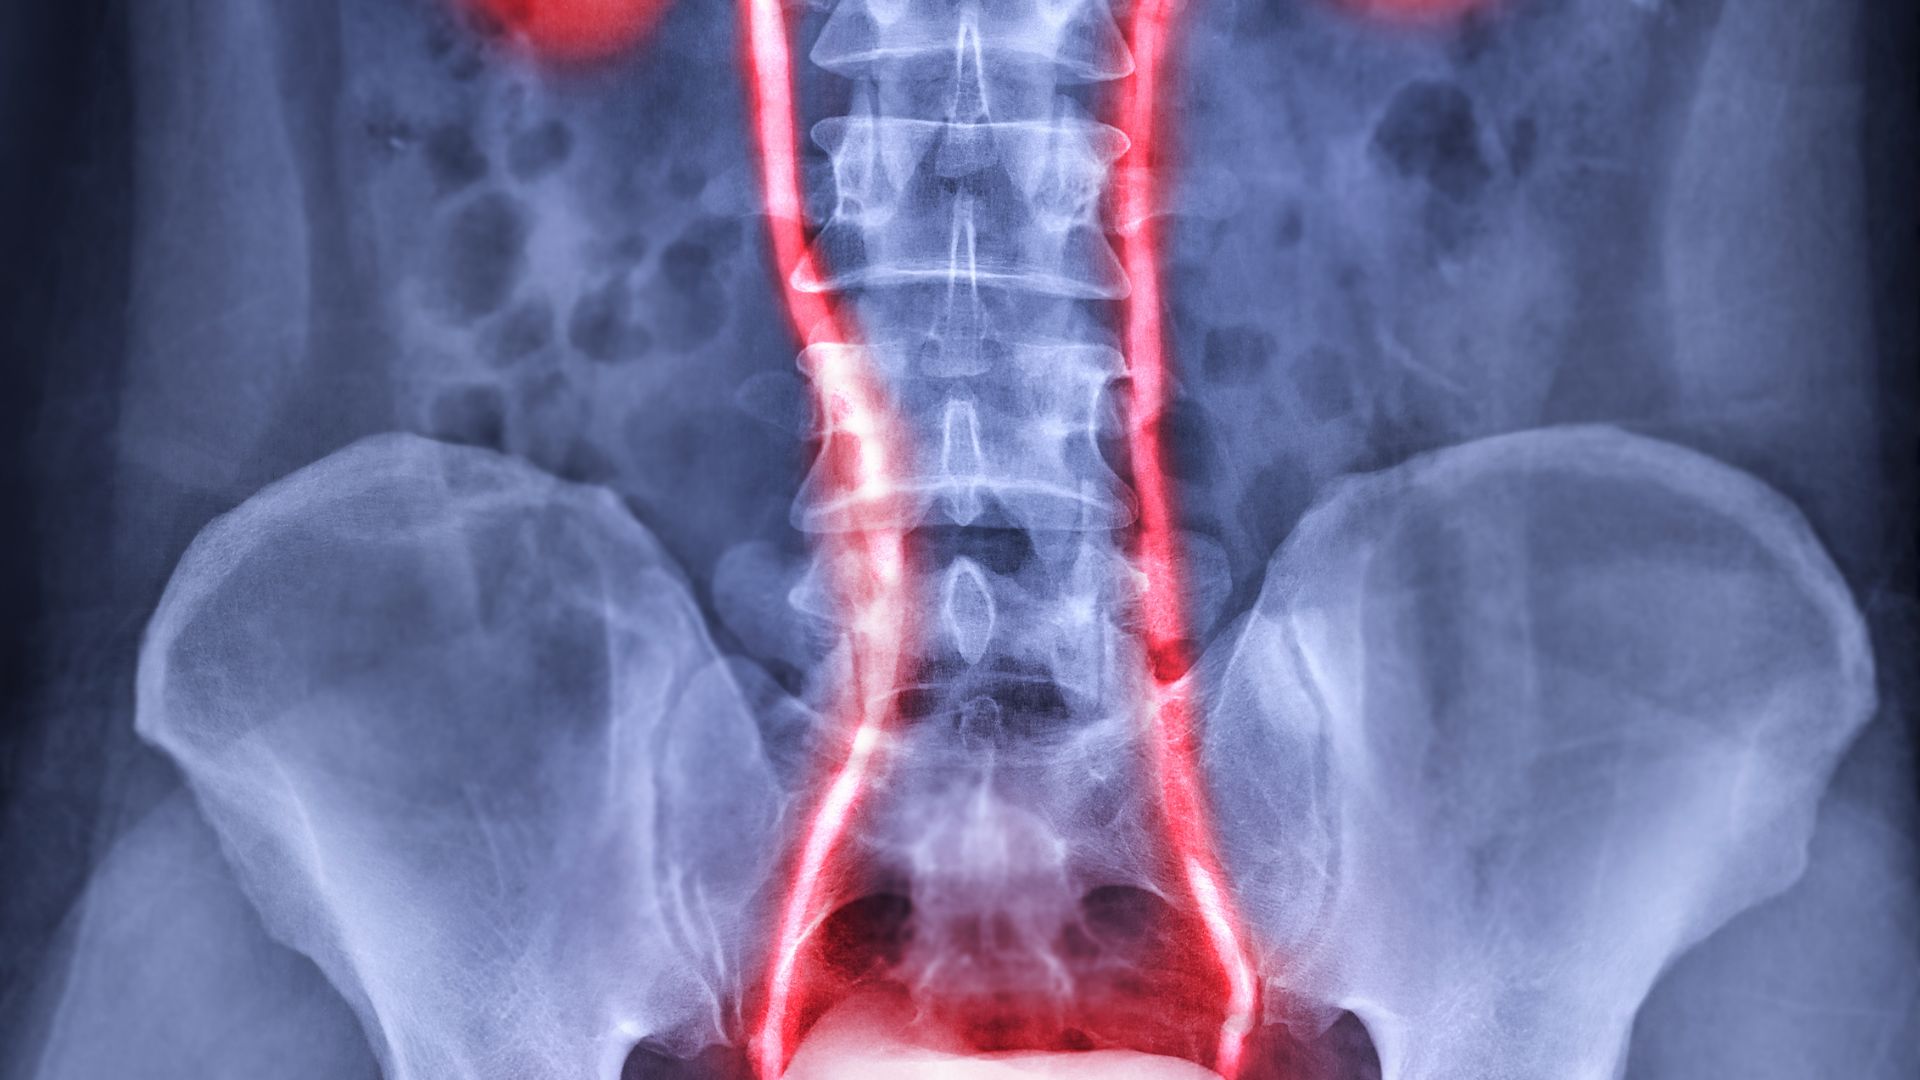

Thận ứ nước trên siêu âm là tình trạng bác sĩ ghi nhận hình ảnh giãn bể thận và/hoặc đài thận khi thực hiện siêu âm hệ tiết niệu. Đây là dấu hiệu cho thấy nước tiểu đang bị ứ đọng trong thận do dòng chảy từ thận xuống bàng quang bị cản trở ở một vị trí nào đó.

Về bản chất, thận có nhiệm vụ lọc máu và tạo ra nước tiểu, sau đó nước tiểu sẽ theo niệu quản xuống bàng quang để được đào thải ra ngoài. Khi quá trình này bị tắc nghẽn hoặc cản trở, nước tiểu không thoát ra được sẽ tích tụ lại trong thận. Sự tích tụ này làm cho các khoang chứa nước tiểu trong thận bị giãn ra và hình ảnh đó được phát hiện qua siêu âm.

Cụ thể, khi bể thận và đài thận bị giãn, hình ảnh trên màn hình sẽ cho thấy các khoang chứa dịch lớn hơn bình thường. Dựa vào mức độ giãn này, bác sĩ có thể đánh giá sơ bộ tình trạng ứ nước và đưa ra chỉ định theo dõi hoặc kiểm tra thêm khi cần thiết.

Dựa trên hình ảnh siêu âm, tình trạng ứ nước tại thận thường được chia thành các mức độ khác nhau. Việc phân độ giúp bác sĩ đánh giá mức độ ảnh hưởng đến thận và quyết định hướng theo dõi phù hợp.